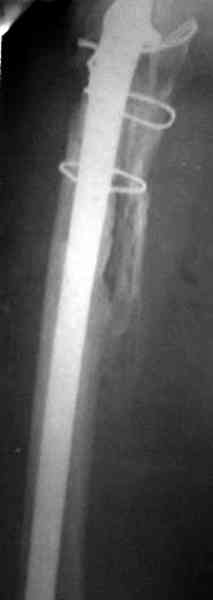

Повторная операция по удалению тотального протеза с irrigation&debridment, канал после очистки цемента обильно промыт и рассверлен римером.

Приготовлен цемент из расчета: Tobramycin 2.4 g (2 флакона), Vancomycin 2 млн (4 флакона) и 2 упаковки цемента с добавлением дополнительного флакона цементной жидкости.

После обработки ацетабулярного компонента, ещё в мягком цементе в полости вертлужной впадины головкой бедренного компонента сделана выемка для головки, чтобы свежий цемент не прилипал к головке. Головку бедренного компонента завернул обычной стерильной фольгой, которую после образования выемки отлепил от головки.

Для спейсера в бедро использовал старый длинный бедренний компонент меньшего диаметра, облепленный со всех сторон цементом с антибиотиком.

Наглухо ушитая рана с дренажом зажила первично, после чего с больной потерял контакт, и только недавно, через 8 лет я осмотрел её. Она без проблем нагружает на конечность и передвигается с помощью трости. От окончательной операции по реконструкции отказывается, довольная результатом.

и последние снимки.